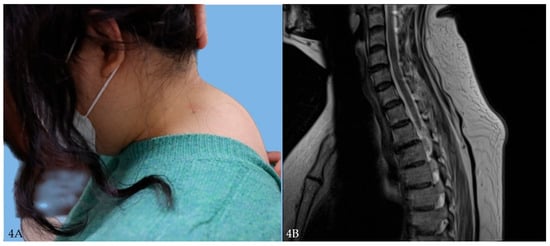

3.1.2. Case 2